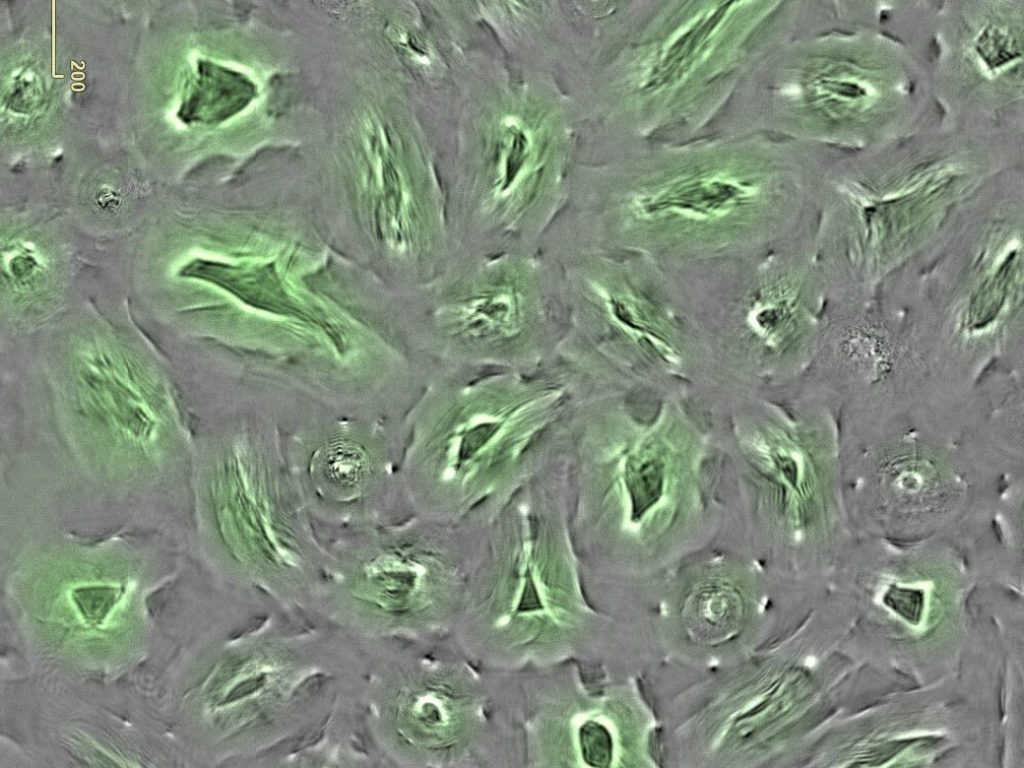

From the cellular mechanisms behind ME/CFS and Long COVID to the evolving science of immune responses and chronic inflammation, each post blends expert analysis, clinical relevance, and plain-language explanations—making the invisible, visible.

Explore methods and tools empowering biomedical research and discovery.